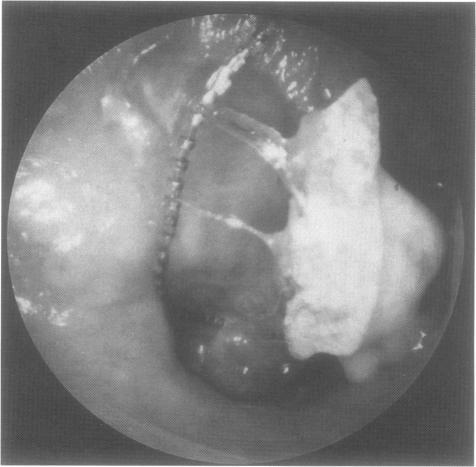

Normally, active chronic suppurative otitis media is regarded as a contraindication for cochlear implantation. In case of a radical cavity after surgical treatment for cholesteatoma, the electrode covered by the epithelial lining of the mastoid will likely become exposed or extruded. Under these circumstances we suggest the subtotal petrosectomy, obliteration of the middle ear cleft with abdominal fat, and the blindsac closure of the external ear canal before cochlear implantation.Fourteen patients with chronic otitis media were successfully implanted with an intracochlear multichannel cochlear implant. After an average follow-up of 28 months a temporary facial palsy in one patient and an insufficient closure of a retroauricular fistula over the mastoid cavity in two cases were observed as postoperative complications. One patient with a tumefactive inflammatory pseudotumor developed a massive inflammation in the implanted ear 2 months after surgery which could not be controlled by conservative treatment. The implant had to be removed and after administration of cyclophosphamide she could be successfully reimplanted 7 months later.Implantation of a foreign body in a potentially infected space which communicates with the endocranium means a surgical challenge which can be managed by obliteration of the middle ear. In case of massive inflammation we prefer a two-stage procedure.

通常情况下,活动性慢性化脓性中耳炎被视为人工耳蜗植入的禁忌证。在胆脂瘤手术治疗后形成根治性鼓室腔的情况下,被乳突上皮衬里覆盖的电极可能会暴露或脱出。在这种情况下,我们建议在人工耳蜗植入前进行颞骨次全切除术,用腹部脂肪封闭中耳腔,并对外耳道进行盲袋封闭。14例慢性中耳炎患者成功植入了鼓室内多通道人工耳蜗。平均随访28个月后,观察到1例患者出现暂时性面瘫,2例患者乳突腔上方耳后瘘管闭合不全,为术后并发症。1例患有肿胀性炎性假瘤的患者在术后2个月植入耳发生严重炎症,保守治疗无法控制。不得不取出植入物,在给予环磷酰胺后,7个月后她得以成功再次植入。在与颅内相通的潜在感染空间植入异物意味着一项手术挑战,可通过封闭中耳来解决。在发生严重炎症的情况下,我们更倾向于采用两阶段手术。